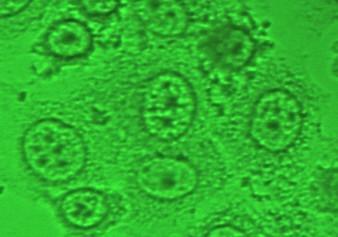

细胞HE染色结果分析